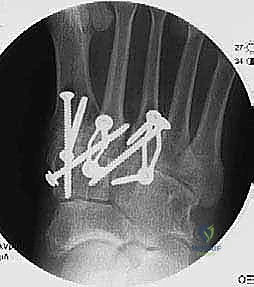

4. Definitive Stabilization: Lag Screws and Compression Staples

Once we are absolutely satisfied with our temporary reduction and alignment, we'll proceed to definitive fixation. The principle here is rigid internal fixation to achieve compression across the fusion sites.

Second and Third TMT Joints Definitive Stabilization:

- "Now, let's move to the second metatarsal. We'll use our cannulated system here. Drill over the guide pin with the appropriate cannulated drill bit for our 3.0-mm cannulated screw. Remember to protect the tibialis anterior tendon during this entire process."

- "Once the pilot hole is drilled, measure your screw length. The bone of the cuneiforms can be softer, so be prepared to use a washer under the screw head if needed to prevent pull-through. Insert the 3.0-mm cannulated lag screw, achieving good compression."

- "Repeat this similar technique for the third metatarsal. Drill over the guide pin with the cannulated drill, measure, and insert the 3.0-mm cannulated lag screw from the third metatarsal into the lateral cuneiform."

- "To further enhance stability and compression, we will now place compression staples. For the third TMT joint, we'll place a compression staple dorsally, spanning the fusion site."

* "And for the second TMT joint, another compression staple dorsally, spanning the fusion site between the second metatarsal and the intermediate cuneiform. This adds robust, broad-surface compression, particularly helpful in the midfoot."